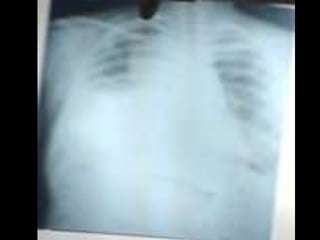

• C’est un téléthorax de face objectivant de multiples opacités de

tonalité hydrique de taille et de formes variables intéressant les

deux champs pulmonaires prédominant au niveau des bases,

confluentes par endroits de plage homogène.

• L’index cardio thoracique ne peut être mesurer, les culs de sacs

pleuraux sont libres et on note l’absence de lésions osseuses

visibles

• Conclusion : syndrome interstitiel et de comblement alvéolaire

réalisant l’aspect en lâché de ballon évoquant des localisations

secondaires.

• Diagnostic différentiel : staphylococcie pleuro pulmonaire

• CAT : TDM thoraco-abdominale, échographie abdomino-pelvienne

et scintigraphie osseuse .Ce bilan d’extension a un double

intérêt : celui de rechercher le néo primitif et celui d’essayer de

déterminer d’autres atteintes